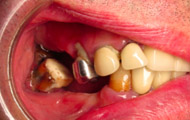

Situation clinique initiale